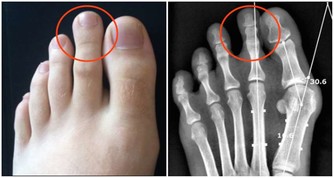

痛風患者能吃魚肉嗎?

想要判定痛風患者能不能吃魚肉,就要看魚肉是不是含有高嘌呤物質。魚的種類有很多種,像一些沙丁魚、鳳尾魚、小乾魚等這類含有高嘌呤物質,建議痛風患者最好不要食用。